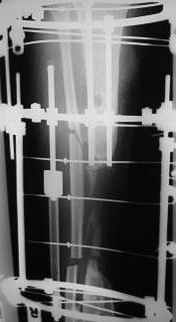

This Patient have to be treated by using Ilizarov bifocal bone transport, aproximatly as showen here.

I would insert a solid titanium locked nail immedialtely after docking. So i would plan previous steps to be done that way not to make additional difficulties for nail insertion, particularly to provide medullary canal in transported fragments. So my choice would be to forget the fibula and do metaphyseal perQ osteotomy of the tibia, transverse or close to, and bone transport. Frame assembly can be discussed if necessary.

I would treat this patient with ilizarov trans osseous osteo synthesis with

distraction at two metaphyseal corticotomies.the reasons being